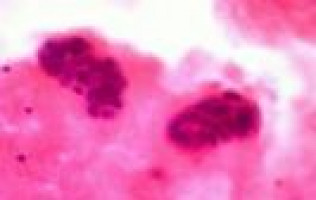

Triple-negative breast cancer (TNBC) accounts for about 15% of all breast cancer cases and is often difficult to treat.

Sacituzumab govitecan, an antibody drug conjugate (ADC), targets the protein Trop2, which is present at high levels on the surfaces of TNBC cells.